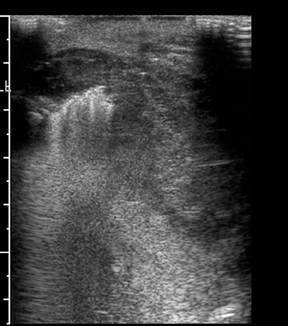

Meera had been experiencing fatigue and unexplained weight gain for months. She dismissed it as stress, but her motherly instincts urged her to seek help. A visit to her doctor led to a thyroid function test, which revealed imbalances that necessitated further investigation through a detailed ultrasound examination. This is where advanced ultrasound services came into play, providing a lifeline to individuals like Meera.

The problem Meera faced was not just practical but deeply emotional. The fear of the unknown and the anxiety of potential illness weighed heavily on her mind. She needed a solution that was not only accurate but also provided peace of mind. The advanced thyroid, scrotal, and breast ultrasound services offered by specialized diagnostic centers became her beacon of hope.

In a country where healthcare accessibility can be a challenge, the availability of such precise and comprehensive diagnostic services is a game-changer. These ultrasound services are equipped with state-of-the-art technology, providing detailed imaging that helps in the early detection and management of various conditions. For individuals like Meera, these services offer reassurance and a clear path forward in managing their health.

What makes these ultrasound services indispensable is their ability to reveal what lies beneath the surface, both literally and figuratively. They provide a sense of control over one’s health, transforming anxiety into action. For Meera, the ultrasound not only identified the cause of her symptoms but also empowered her with the knowledge to take charge of her health. Her treatment plan became clear, and the fog of uncertainty began to lift.

Moreover, these services are not just a boon for individual patients. They also assist healthcare providers in delivering more accurate diagnoses and personalized treatment plans. Dr. Anil Kumar, a renowned endocrinologist in Bangalore, emphasizes the importance of such diagnostic tools. He shares, “Advanced ultrasound services have revolutionized the way we approach patient care. They provide us with a detailed map of the patient’s condition, enabling us to make informed decisions that can significantly impact outcomes.”